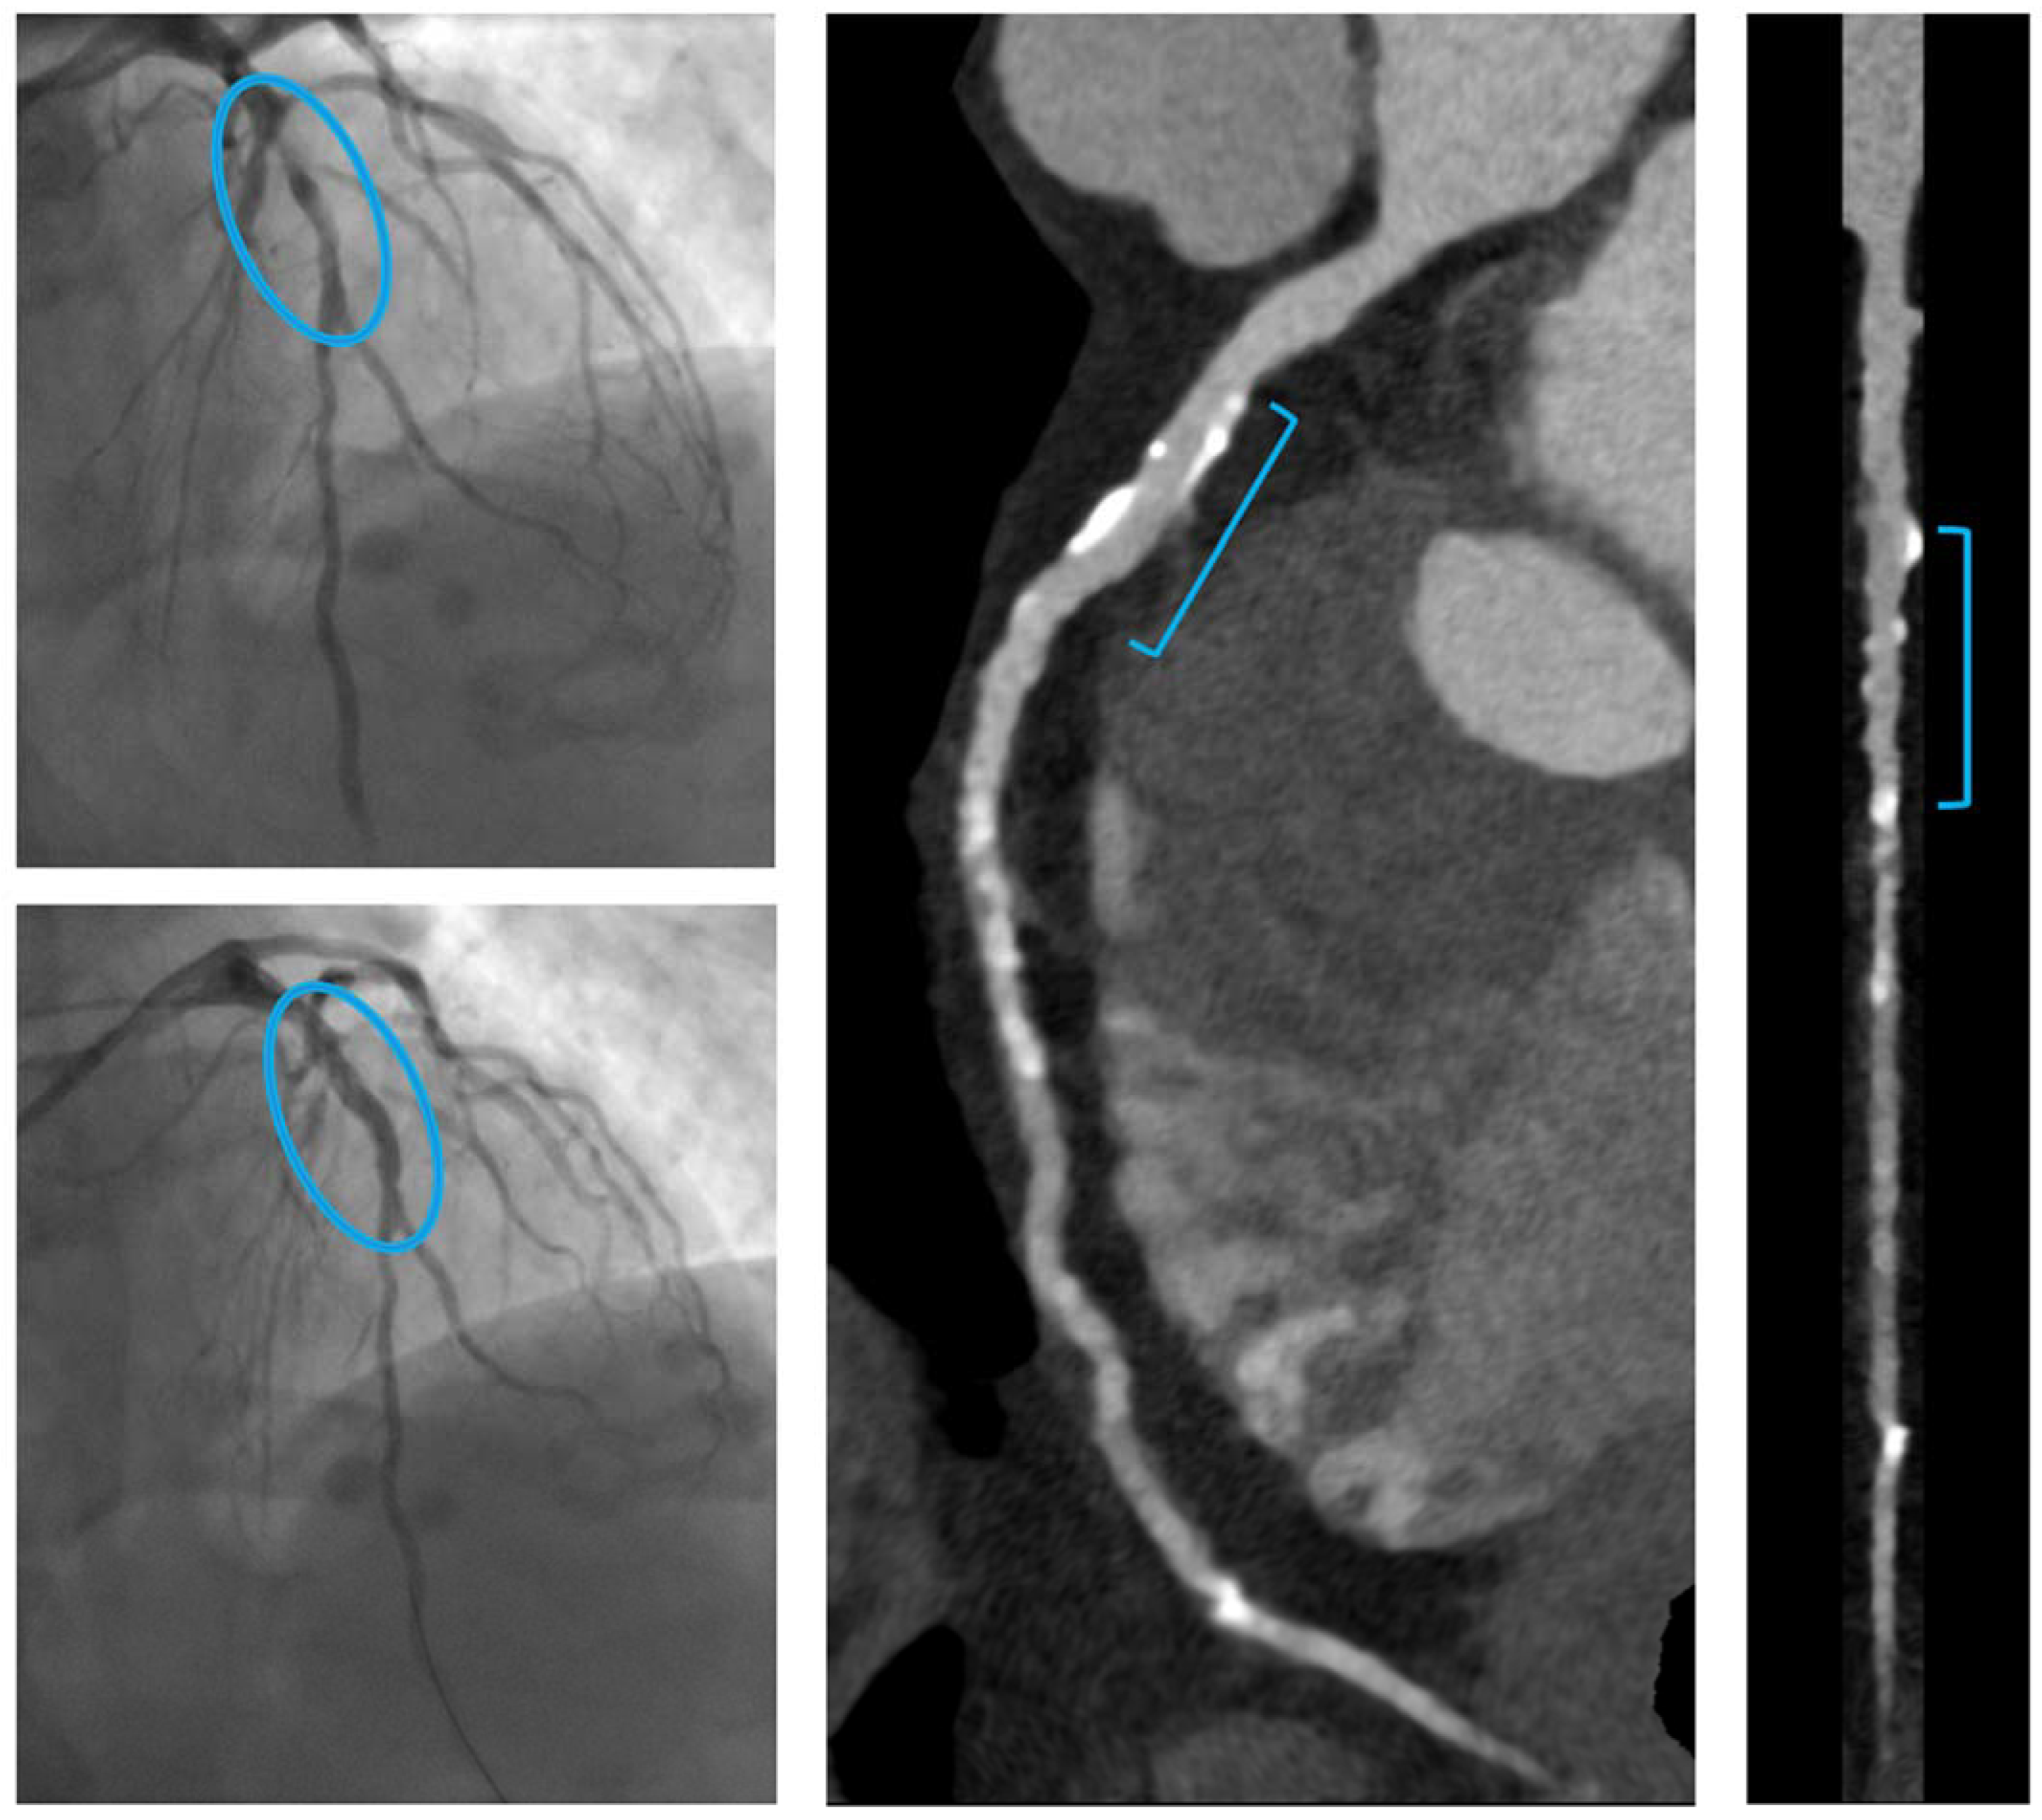

- B.

- A patient with significant stenosis at the bifurcation LAD-first diagonal branch, treated with one RMS on the LAD and balloon on the first diagonal branch (Magmaris® 3 × 25 mm).